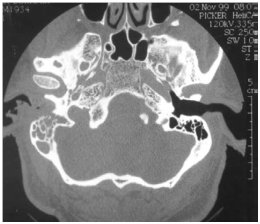

Figure 1 Axial scanner (TDM) in a patient aged diabetes, refereen reason for the paralysis of the facial nerve that has grown despite the oral treatment. The scanner shows the right temporal bone destruction. Note the disappearance of the posterior wall of the external ear canal (short arrow). Mastoid air cells are secondarily involved and clouded (long arrow) from the left side well ventilated.

The MEO is an otological infection that has life-threatening complications. It is considered as a complication of external otitis.2 Occurs mainly in the elderly who have diabetes or another condition that compromises the immune system. Doctors must be able to recognize this infection, initiate treatment, and refer patients to an Otolaryngologist. The precise etiology of this condition is unknown, but theories related to impaired immunity, the local tissue microangiopathie and even modified biochemistry of earwax have been proposed. Infection of the soft tissues of the external ear canal is common, especially in hot and humid climates. The usual triggers are trauma (often caused by q-tips) and exposure to the pool of water. The most frequently found germ is Pseudomonas aeruginosa, is not a normal germ of the EEC.3 Other possible germs include Staphylococcus epidermidis,4 gram negative bacteria and fungi. External otitis patients complain of earache and sensitivity to atrial movement. The otorrhoea may be present, the obliteration of the external ear canal by edema and secretions can cause hearing loss, or a feeling of fullness in the ear. The disease comes from the EEC and propagates through the osteo-cartilaginous junction to involve soft tissue under the temporal bone. Granulation tissue is usually present in the EEC. The spread of the infection can cause thrombosis of the lateral sinuses and petrous sinus upper and lower. Initially, the progressive skull base osteomyelitis can cause cranial Polyneuropathy, paralysis of the facial nerve being the most common; cranial nerves IX, X, and XI (the jugular foramen syndrome) nerves and cranial nerve XII (hypoglosse channel) are less often involved with the development of the sphenoidal sinusitis. Imaging to show the extension of the infection to the bony structures is usually required to establish the diagnosis of MEO6 imaging modalities include tomographic (CT) scan, scan bone to the technetium Tc99m medronate methylene diphosphonate, and scintigraphy to Ga 67 gallium citrate. CT is used to determine the location and extent of diseased tissue (Figure 1 & Figure 2). The temporal bone is the first os to be affected, with an imminent involvement of petrous apex and the mastoid process. Extratemporal extension has become rare since the introduction of powerful antibiotics. In evaluating the scanner, it is important to remember that at least one third of the minerals is lost before the radiological changes are becoming apparent; Conversely, the bone remineralization continued long after that infection is Gueriela scan is a diagnostic sensiblemais non-specific to the MEO, if to the 67Ga scintigraphy is available, (Figure 3). It must be used for the initial diagnosis and follow-up tool.7 Using in combination imaging modalities, it is possible to prove that the temporal bone is reached (scan and bone scan to the 99mTc) with infectious process (Ga 67 scintigraphy).6 MRI is of interest in advanced forms allowing a better analysis of the deep spaces of the face, the nervous foramina, merien hard spaces and the Medullary bone in the base of the skull.